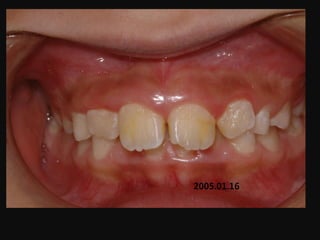

J.S.Kim

1996.5.15 / M

C.C

• Max. protrusion

Dx

• Deepbite caused by mentalis activity

Goal

• Establish normal swallowing pattern with T4K

2005.01.16